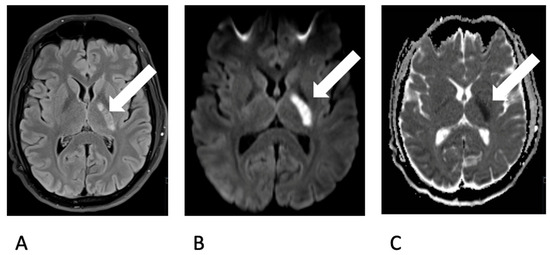

As the herpes simplex virus and Listeria tests PCR yielded negative results, the administration of aciclovir and ampicillin was discontinued. A follow-up MRI revealed inflammatory changes in the region of the right jaw joint and the masticatory muscles (Figure 3).

Figure 3.

Contrast enhanced axial T1 SPACE showing a marked inflammatory contrast enhancement of the mandible head and the surrounding soft tissue, especially the lateral pterygoidal and masseter muscle.